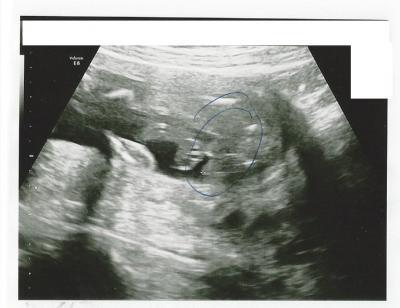

Hallihallo! Wir kommen grade vom Frauenarzt (20+0) wo wir auf die Frage, ob unser Bauchbewohner ein Mädchen oder ein Junge wird, ein Bild in die Hand gedrückt bekamen ohne einen weiteren Kommentar. Der Arzt hat was da eingekringelt aber wir können nichts erkennen bzw. wir haben nur eine Vermutung aber icandererseits sieht es in Relation zum Baby dann doch zuuu große aus...Wie es auch sein mag, ich will Euch nicht beeinflussen. Was meint Ihr? Junge oder Mädchen? Danke Euch!

Blöd gefragt aber woran macht Ihr es denn fest? Das "schwarze" ist ja sicherlich nicht das Kind aber an welcher Stelle sieht/ erahnt man einen Penis? Tut mir Leid, aber egal wie ich das Bild drehe, erkenne ich da weder Schamlippen noch einen Penis

Ich sehe da nix, was auf einen Jungen schließen läßt... Eindeutig jedoch sehe ich die Nabelschnur... vllt seht ihr darin den Penis??? Das wäre so wie du schon schreibst viiiieeeellll zu groß im Verhältnis zum Baby!

Huhu, also ich finde es sehr schwierig was zu erkennen, da die Position nicht optimal ist. Aber egal wie oft ich es vergrößere denke ich das es ein Mädchen ist. Diese zwei Knubbel die man da sieht sehen aus wie die Oberschenkel und der schwarze spalt dazwischen sieht man nichts außer schwarz (Fruchtwasser) und keinen Zipfel (Penis). Der schwarze Strich im Kreis könnte ein Harnleiter sein, der mit urin gefüllt ist. Aber es ist nur ne Vermutung. LG Diana